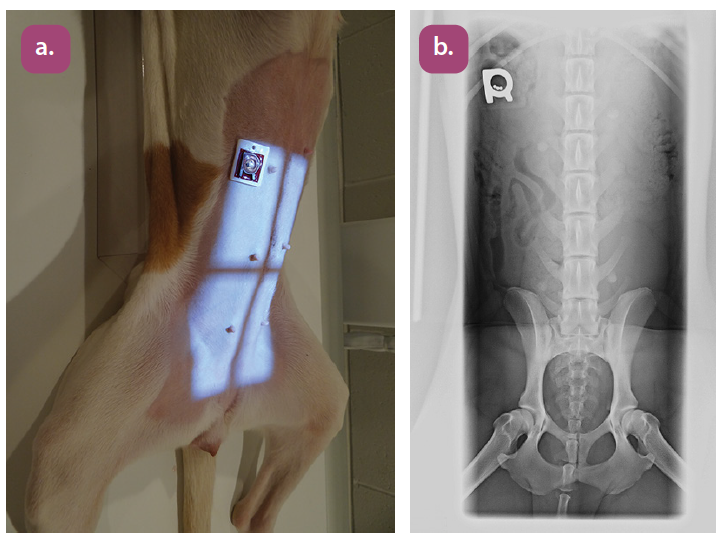

ventrodorsal lumbar spine projection

lateral lumbar spine projection